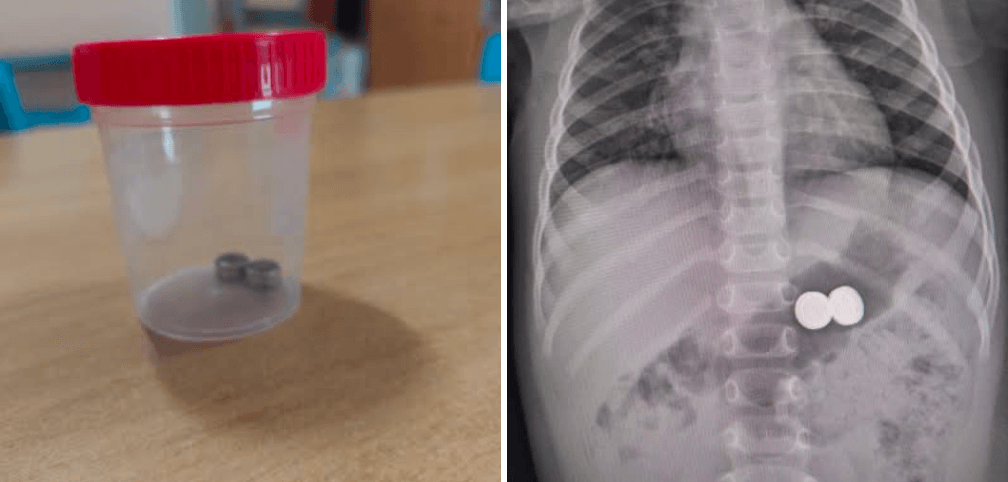

Bambina di 1 anno ingerisce batterie a bottone, operata d’urgenza

Una bambina di un anno è stata condotta d’urgenza all’ospedale Garibaldi-Nesima, dopo aver ingerito due batterie a bottone. Il pronto…